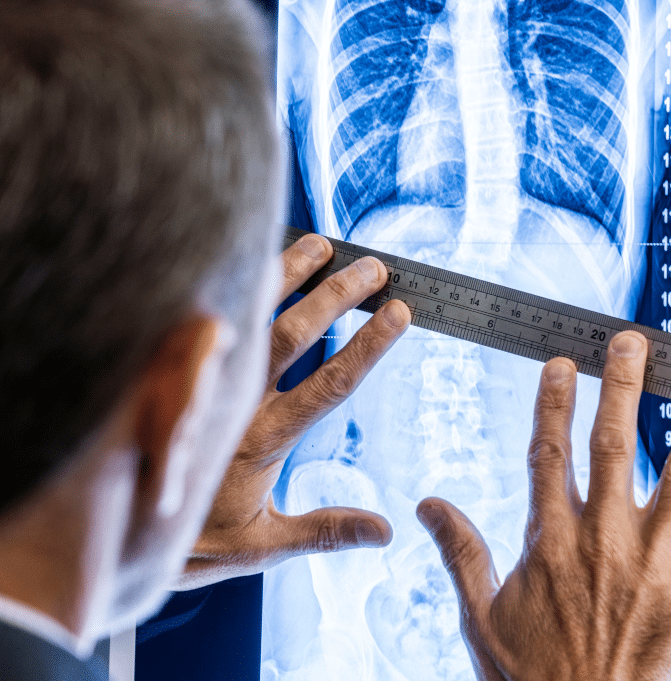

We start with a thorough scoliosis assessment with one of our clinicians, which includes a review of X-rays and medical history, and discussion about any concerns and goals.

After the assessment, a personalised treatment plan will be developed. The treatment options suggested will depend on a multitude of factors such as age, the severity of the curve and current symptoms, and could include recommendations for bracing, specific exercise rehabilitation (ScoliBalance®) or surgery, if that is in the patient’s best interest.